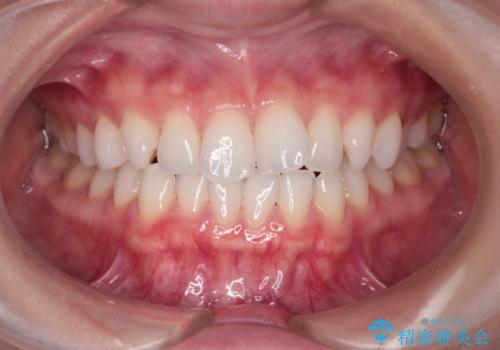

[ 引っ込んだ前歯を治したい ] 歯を抜かないマウスピース矯正

![[ 引っ込んだ前歯を治したい ] 歯を抜かないマウスピース矯正の症例 治療前](https://seimitsushinbi.jp/wp/wp-content/uploads/2024/03/IMG_1089-500x350.jpg?v=1711680738)

![[ 引っ込んだ前歯を治したい ] 歯を抜かないマウスピース矯正の症例 治療後](https://seimitsushinbi.jp/wp/wp-content/uploads/2024/03/5329ad9ea362646e5d4ee5f7b30cf319-500x350.jpg?v=1711680954)